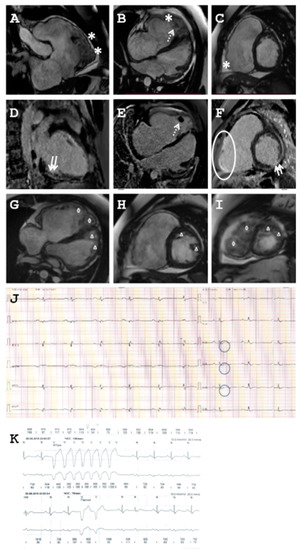

2.1. Clinical Description of the Patients

2.1.1. Family A

2.1.2. Family B